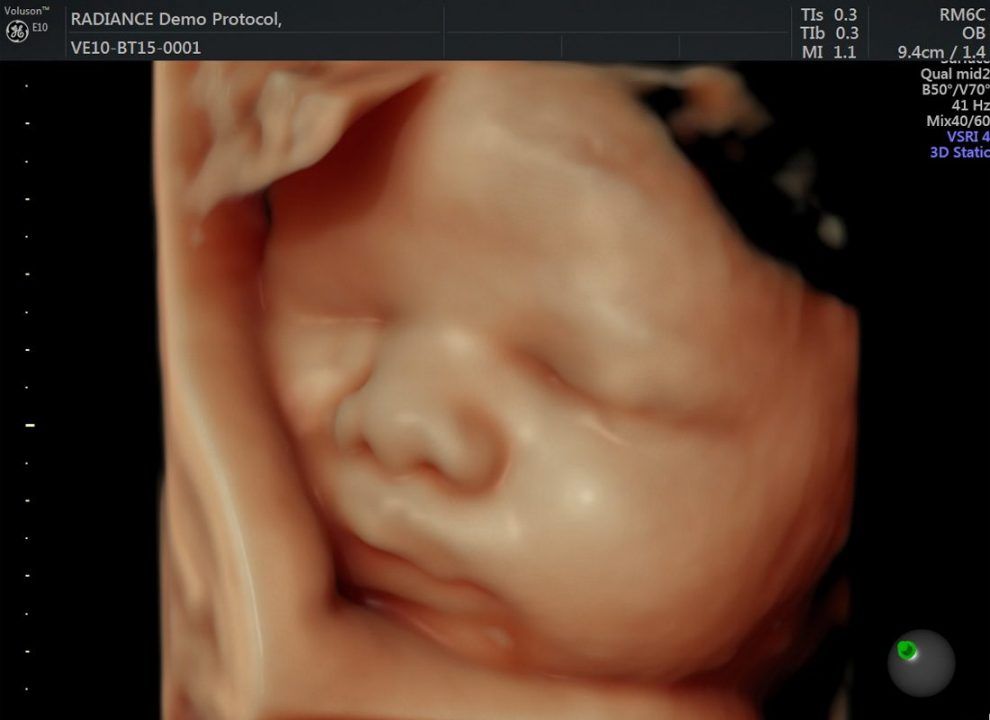

Acum fatul poate fi evaluat inca din primele etape de dezvoltare cu imagini 2D, 3D si 4D care descriu cele mai mici detalii cu o rezolutie inalta si permit masuratori mai exacte.

Este un ecograf perfect pentru femeile insarcinate si pentru tatii care, dupa ce au aflat ca totul este bine, isi doresc experienta unica si emotionanta a primei fotografii a copilului lor – aceea de a vedea fata bebelusului lor intr-o imagine 3D/4D de cea mai buna calitate.